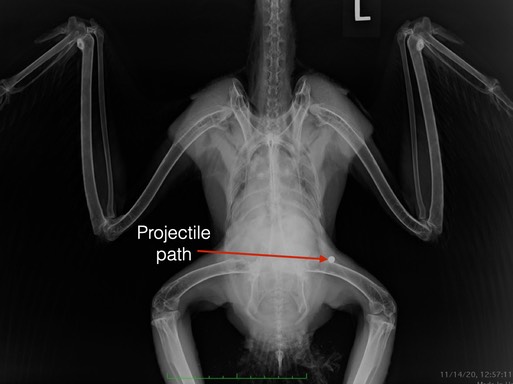

Red-tailed Hawk 20-584

On Saturday, an adult Red-tailed Hawk was found in a pasture in a rural part of Kennewick, WA. Her legs were paralyzed. She had a small wound above her right hip. A radiograph showed a projectile lodged near her left hip. It had past through her spine, causing the paralysis. If you look closely at the projectile you will notice it’s shape is slightly deformed, indicating it is made of lead. You can also see, like the owl, the hawk is in excellent body condition. She was also providing free rodent control to the agricultural community.